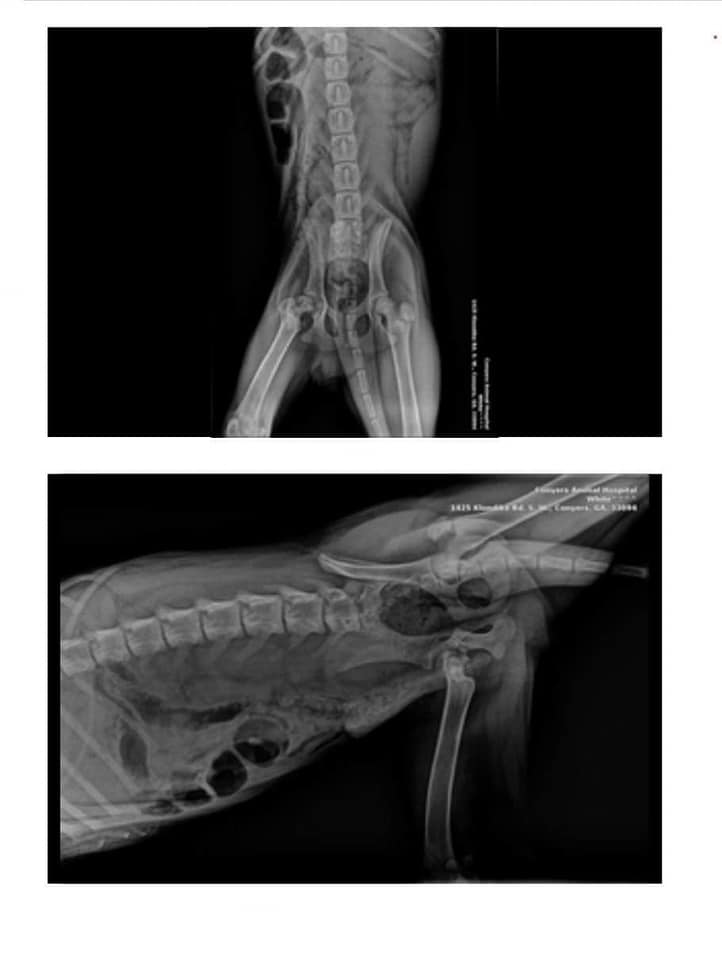

According to a Facebook post, Hank was also found with a broken leg that had been broken for at least two weeks.

Hank was taken in by Humans and Animals United, a Florida-based nonprofit animal rescue organization, who prepared him for a surgery to fix his broken leg.